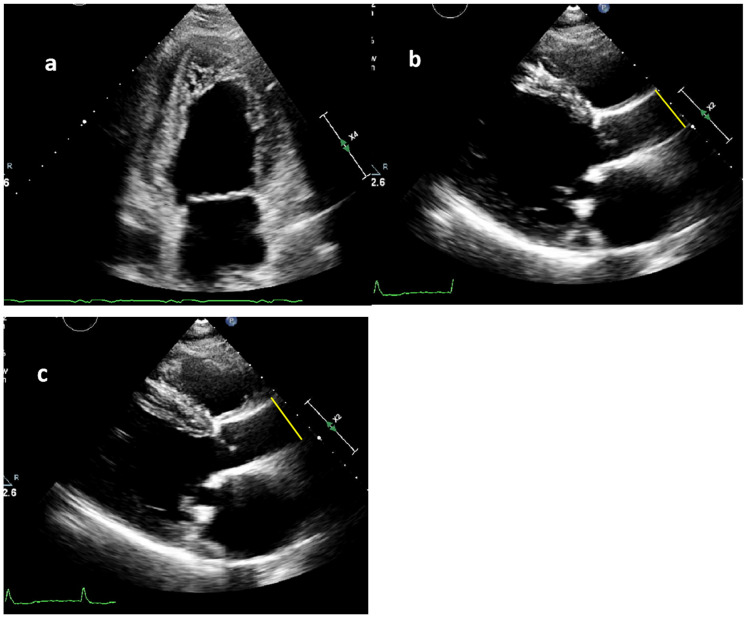

Abnormal aortic elasticity serves as a marker for cardiovascular mortality and has a negative impact on the left ventricular (LV) afterload. Noncompaction cardiomyopathy (NCCM) is characterized by hypertrabeculation of the LV endomyocardial wall, with an underdeveloped endocardial helix. This may result in absence of LV twist, disturbed aortic elasticity, LV dysfunction, and ultimately premature heart failure (HF). This study compared the aortic stiffness and clinical outcome in patients with NCCM to that of a control group with dilated cardiomyopathy (DCM). Sixty NCCM patients, matched by age and sex, were compared with 60 DCM controls. Transthoracic echocardiography was performed to measure the systolic (SD) and diastolic diameters (DD) of the ascending aorta. These measurements, along with systolic (SBP) and diastolic blood pressure (DBP), were utilized to calculate the aortic stiffness index defined as ln(SBP/DBP)/[(SD-DD)/DD]. This index was then compared to clinical features and outcome. The mean age was 49 ± 16 years (55% males) in the NCCM group and 49 ± 16 years (55% male) in the DCM group. Aortic stiffness index (ASI) was significantly higher in the NCCM group than in the DCM group (7.0 [5.8-10.2] vs. 6.2 [4.8-7.7], p = 0.011). This difference remained statistically significant after adjustment for established risk factors associated with aortic stiffness (β = 1.771; 95% CI [0.253-3.289], p = 0.023). Patients with NCCM demonstrated increased aortic stiffness when compared to those with DCM, which may reflect the underlying pathophysiological processes. Additional research is necessary to evaluate the impact of aortic stiffness on the advancement of LV dysfunction, the onset of heart failure, and long-term outcomes.